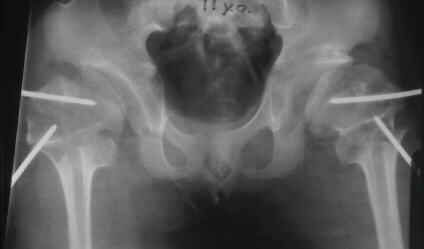

SPONDYLO-EPI-METAPHYSEAL DYSPLASIA WITH JOINT LAXITY (SEMDJL)

Radiographic features: